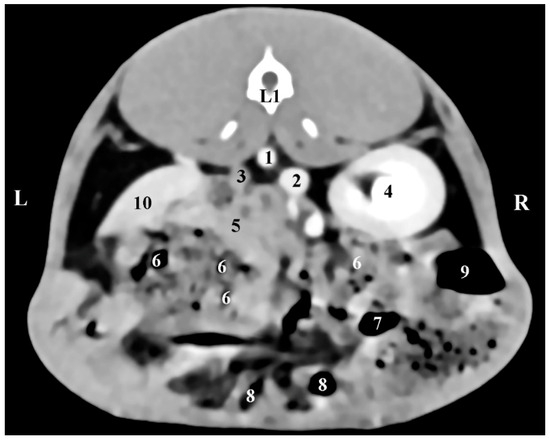

The transverse post-contrast CT anatomical investigation at the level of the 12th thoracic vertebra (Th12) gave complete information about the topographic location and shape of the right adrenal gland. The latter was a retroperitoneal soft tissue finding located in the intrathoracic part of the abdominal cavity. The gland was localized on the right of the median plane, in the dorsal abdominal quarter. It was detected dorsally and in close proximity to the contrast-enhancing v. cava caudalis, the aorta abdominalis, and the liver. The borders of the right adrenal were sharply delineated, which defined it as an ellipse-shaped structure. The soft tissue attenuation of the gl. adrenalis dextra was relatively lower than that of the right liver lobe (Figure 1).

The left adrenal gland was visualized at the level of the 1st lumbar vertebra (L1). It was left to the median plane and in the dorsal abdominal cavity quarter. The gland was visible at a more caudal level of scanning compared to the right adrenal. gl. adrenalis sinistra had oval contours and was observed ventrally to the contrast-enhancing abdominal aorta and distant and craniomedially to the left kidney. The left adrenal density was similar to that of the ventrally located mesentery (Figure 2).

Figure 1. Transverse CT post-contrast anatomical study of the rabbit abdomen at the level of Th12. L—left; R—right. (1) aorta abdominalis; (2) v. cava caudalis; (3) right adrenal gland; (4) lobus hepatis dexter; (5) caecum; (6) duodenum; (7) ileum; (8) corpus ventriculi; (9) fundus ventriculi.

Figure 2. Transverse CT post-contrast anatomical study of the rabbit abdomen at the level of L1. L—left; R—right. (1) aorta abdominalis; (2) v. cava caudalis; (3) left adrenal gland; (4) right kidney; (5) small intestine; (6) mesenterium; (7) colon descendens; (8) colon ascendens; (9) caecum; (10) lien.